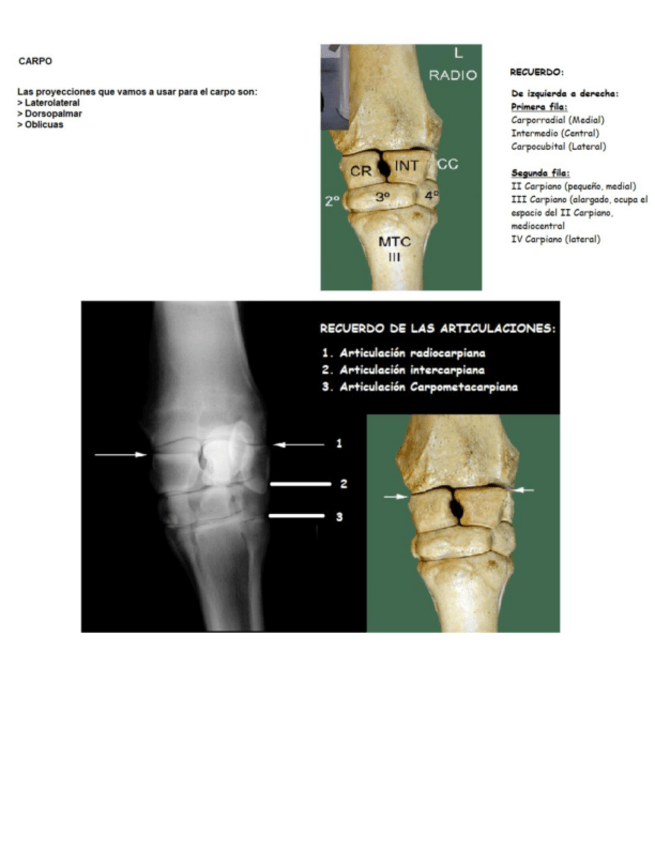

Apuntes - radiografia-pequenos-animales.pdf

55 páginas